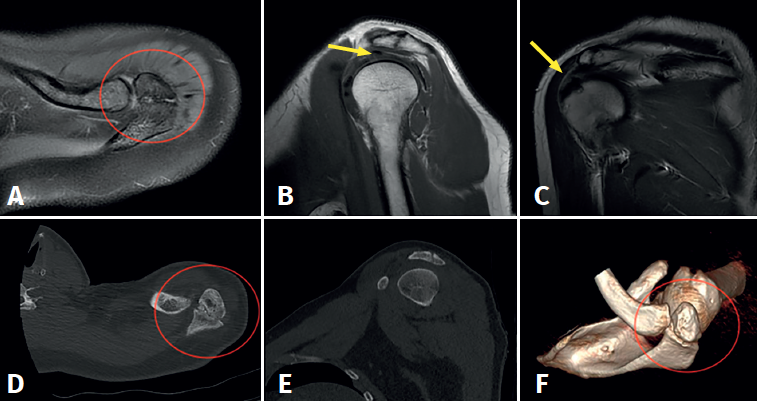

Figure 1. Left shoulder. Preoperative radiographic view showing a "double density" sign (red circle) suggestive of os acromiale.

The basic imaging diagnostic explorations should include anteroposterior, axillary and scapular Y projection radiographs(Figure 1), with the axillary view being the most useful option in this regard(8). Magnetic resonance imaging (MRI) can identify additional disease conditions such as concomitant rotator cuff injury, for example(9). The presence of bone oedema in axial sections in fat-suppressed T2-weighted sequences is an expected sign in the MRI assessment of symptomatic os acromiale (Figure 2).

Figure 2. Preoperative magnetic resonance imaging and computed tomographic views showing deformation of the distal extremity of the acromion with the presence of an acromial ossicle of irregular morphology (images A, D and F, red circle) associated to incipient supraspinatus tendinopathy, with enhanced signal intensity of the tendon in the bursal surface (images B and C, yellow arrow).